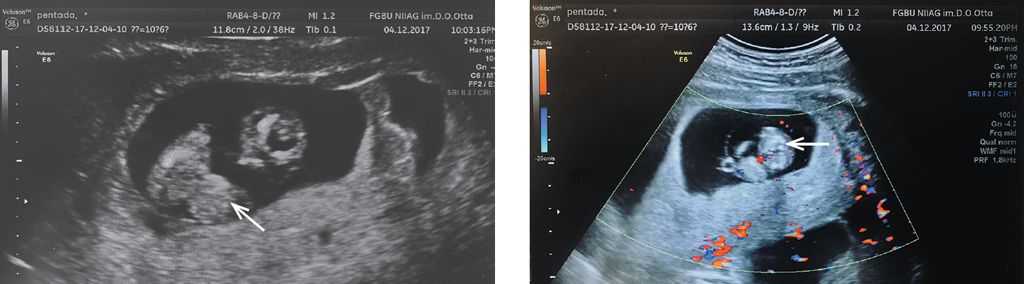

При рутинном ультразвуковом трансвагинальном и трансабдоминальном исследовании ультразвуковым сканером Voluson E6 (GE) при сроке беременности 10 недель в полости матки обнаружены два живых подвижных плода, копчико-теменные размеры плодов соответствовали 10–11 неделям беременности. Ультразвуковая оценка анатомии первого плода выявила супраумбиликальный дефект передней брюшной стенки, дефект диафрагмы и дефект грудной клетки с образованием грыжевого мешка. Также было обнаружено дистопическое положение сердца вне грудной полости первого плода. В составе грыжевого мешка обнаружены следующие органы плода: петли кишечника, сердце и часть печени (рис. 1). Сердцебиение плода было ритмичное, перикард не визуализировался. Оценить внутрисердечные структуры не удалось. Ультразвуковых признаков врожденных пороков развития второго плода выявлено не было. Хорион первого плода располагался по передней стенке матки, а второго плода — по задней. Обнаруженные ультразвуковые признаки соответствуют врожденной аномалии плода — пентаде Кантрелла [8, 9]. Кроме того, по передней стенке матки визуализировались два участка отслойки плодного яйца размером 37 × 9 и 39 × 15 мм в стадии организации. Длина цервикального канала составила 45 мм, внутренний зев закрыт. Размеры яичников по-прежнему были увеличены: правый — 113 × 68 × 76 мм (V = 303,7 см3), левый — 90 × 54 × 67 мм (V = 169,3 см3), в них обнаружены множественные жидкостные полости и желтые тела диаметром до 25 мм.

Рис. 1. Беременность 10 недель 6 дней. Эхограмма плода с множественными врожденными пороками развития. Грыжевой мешок, образовавшийся вследствие дефектов передней брюшной стенки и грудной клетки плода, дистопическое положение сердца плода в составе грыжевого мешка (отмечены стрелками)

Fig. 1. 10 Weeks 6 days of pregnancy. Echogram of the fetus with multiple congenital malformations: the hernia sac formed due to defects of the anterior abdominal wall and chest of the fetus; the dystopian position of the fetal heart as part of the hernia sac (marked with arrows)